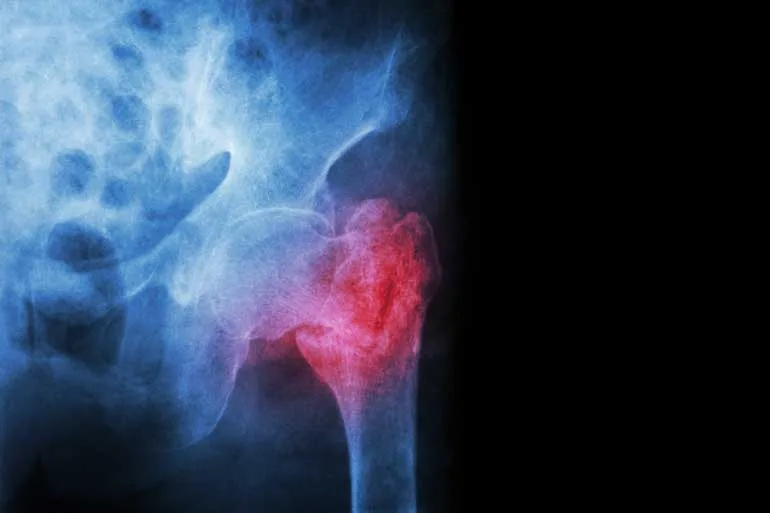

- Restaurando a mobilidade: Após a cirurgia, o paciente apresenta mobilidade limitada e amplitude de movimento reduzida. Os exercícios trabalhados na fisioterapia são destinados a restaurar o movimento articular do membro ou a área lesionada otimizando sua capacidade de movimento.